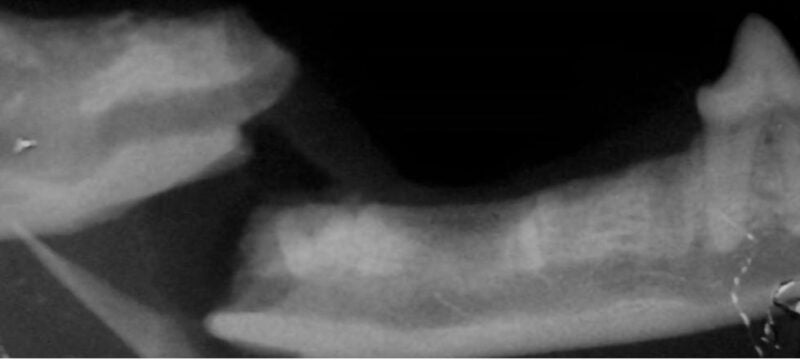

Dental X-ray

This VDOS webinar will review the management of the most common complications that can occur during tooth extraction in dogs and cats, including fractured roots, hemorrhage, trauma to adjacent structures, fracture of the alveolus or jaw, oronasal fistula, trauma from opposing teeth, emphysema and air embolism, and local and systemic infection. The didactic lecture will last 1.5 hours, but the webinar is designed so that there is extra time for interactive participation and answering your questions.